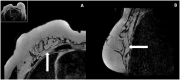

The surgical procedure of AFT and follow-up with imaging modalities including mammography (MG), ultrasound (US), and MRI in patients with a total breast reconstruction with AFT are summarized to illustrate the radiological normal and suspicious findings for malignancy.

Imaging after a total breast reconstruction with AFT appears to be based mostly on benign imaging findings with an overall low biopsy rate. As higher volumes are injected in this technique, the risk for the onset of fat necrosis increases. Imaging findings most often are related to fat necrosis after AFT. On MG, fat necrosis can mostly be seen as oil cysts. The occurrence of a breast seroma after total breast reconstruction with AFT is an unfavourable outcome and may require special treatment. Fat deposition in the pectoral muscle is a previously unknown, but benign entity. Although fat necrosis is a benign entity, it can mimic breast cancer (recurrence).

In symptomatic women after total breast reconstruction with AFT, MG and US can be considered as first diagnostic modalities. Breast MRI can be used as a problem-solving tool during later stage. Future studies should investigate the most optimal follow-up strategy, including different imaging modalities, in patients treated with AFT for total breast reconstruction.